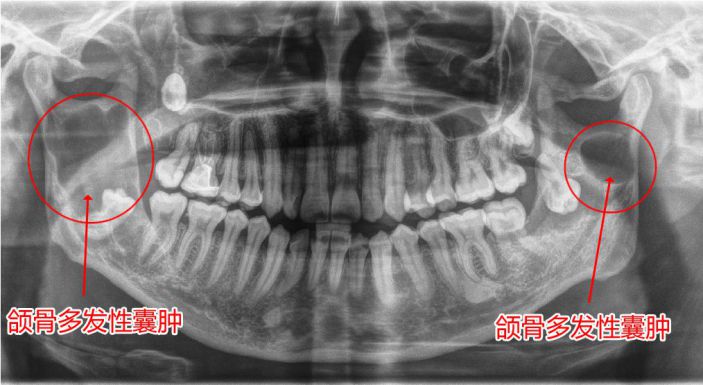

△經西諾德3D口腔全景CT檢查發現颌骨多發性囊腫

颌骨囊腫是指在颌骨内出現一含有液體的囊性腫物,逐步增大、颌骨膨脹破壞。初期無自覺症狀,若繼續生長,骨質逐漸向周圍膨脹,則形成面部畸形。西諾德3D口腔全景CT有助于颌骨囊腫的早診斷、早治療。